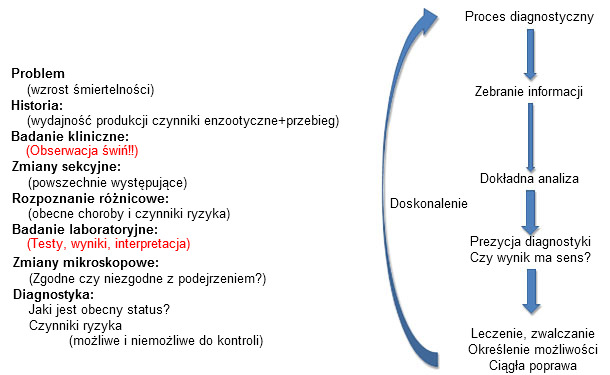

Testy diagnostyczne to narzędzia dla doświadczonych w interpretacji użytkowników, wykorzystywane w określonym kontekście klinicznym. Prawidłowe wykorzystanie tych narzędzi jest możliwe jedynie w sytuacji ich zastosowania w połączeniu z innymi elementami procesu rozpoznawczego. Obserwacje czy wyniki badań, które „nie mają sensu” powinny prowadzić do głębokiej analizy procesu diagnostycznego i ewentualnie dalszych badań (ryc. 3). Jest to w teorii proste ale w praktyce często pomijane. Przypuszczenia, nastawienie na spodziewany wynik, powierzchowna analiza może prowadzić do błędnych wniosków diagnostycznych.

Ryc. 3: Proces diagnoistyczny: wszystkie obserwacje powinny układać się w logiczną całość